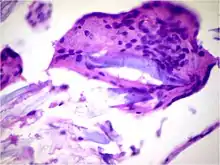

![]() | Carcinoma in situ | CIN-III (HSIL) showing diffuse severe atypia with loss of maturation involving full thickness of epithelium with intact basement membrane. | Category: Histopathology of carcinomas in situ | Carcinoma in-situ |